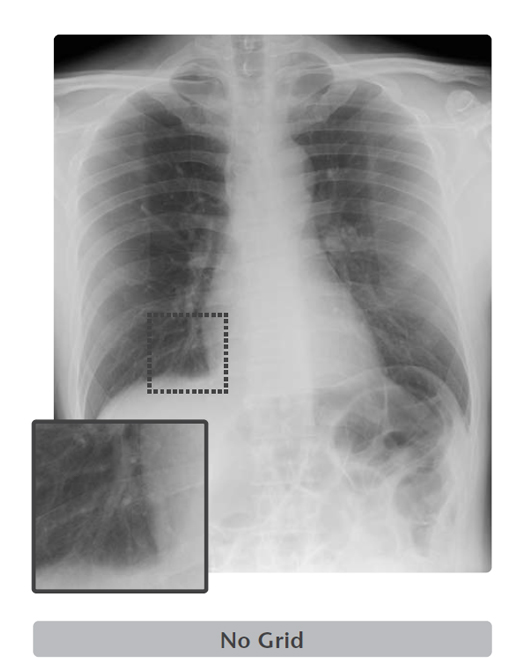

Image processing that remove the scatter X-rays from the digital radiography created without a physical grid.

Virtual Grid is an image processing software that corrects for the effects of scatter X-rays that otherwise reduce image contrast and clarity.

Without the need for physical grid, this software quickly predicts and then corrects for the effects of scatter X-rays, creating an improved image quality.

High quality images can be obtained under low dose conditions, thus reducing the amount of radiation does the patient receives*4.

- *4 In CD-RAD phantom evaluations performed by FUJIFILM, when compared with images acquired with an 8:1 grid, comparable non-grid images processed with Virtual Grid software yielded a 50% reduction in dose.

Virtual Grid allows setting of the grid ratio, number of grid lines and interspace material, and examinations using the appropriate grid conditions.

Just as for a physical grid, different Virtual Grid settings can be used, best suited for the different regions and exposure conditions.

Of course, as it is a virtually created grid, the grid type can be changed after an exposure